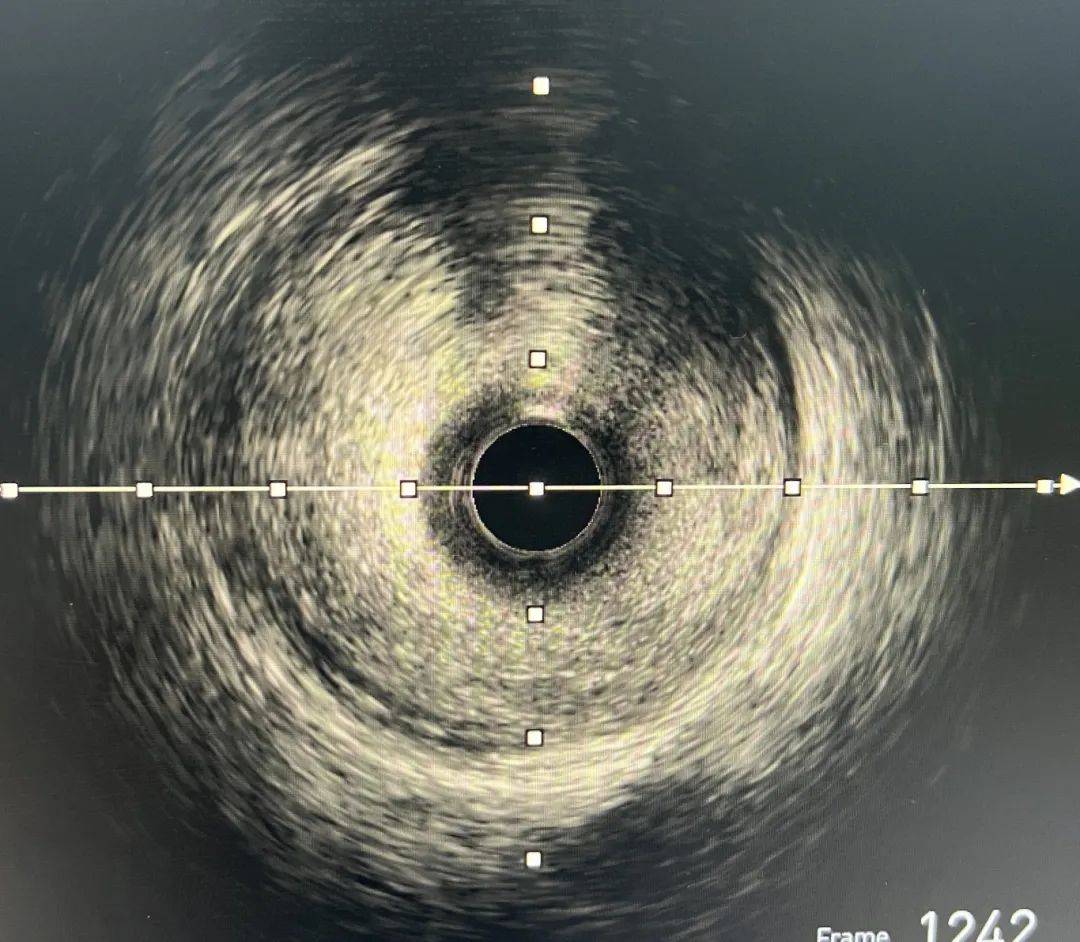

高效「心」技術——「無煙PCI」

無煙PCI就是不使用造影劑的介入技術,醫生應用IVUS(血管內超聲),充當「眼睛」指導手術,這對手術團隊是一項挑戰。造影劑在冠脈介入手術過程中就是醫生的透視眼,採用「無煙技術」對血管、導絲、球囊、支架的定位要求極高,術者必須有對冠脈疾病的理解及冠脈腔內影像學過硬的技術,才可以成功完成手術。

術中,介入團隊在院長林海龍的指導下,對王大爺實施IVUS檢查,發現右冠脈中段嚴重狹窄,斑塊負荷86%,應用多導絲定位及解剖定位方式,精準測量,在未使用1滴造影劑的情況下,僅用時40分鐘成功為患者植入2枚支架,複查IVUS提示狹窄解除,支架貼壁良好。術後患者胸痛症狀緩解,順利出院。